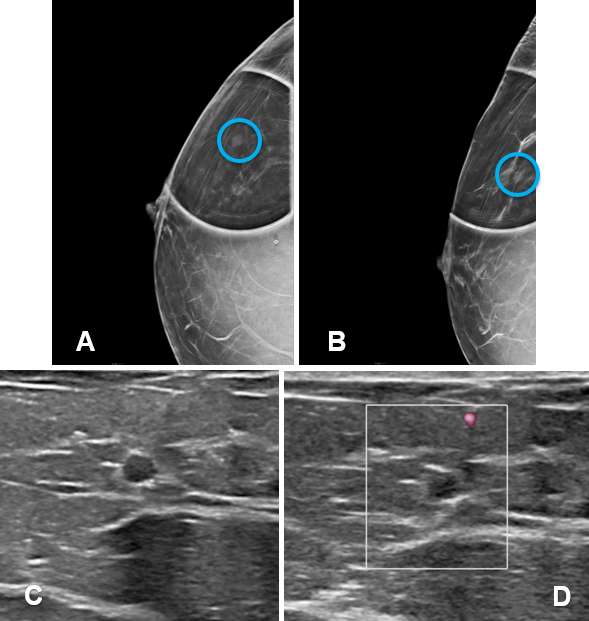

Mammography - Mammography often plays a complementary role in the assessment of simple breast cysts. They typically appear as well-circumscribed, oval or round, low density masses on mammogram. The density is often similar to that of surrounding fibroglandular tissue and background parenchymal elements are often discernible through the mass. Absence of associated microcalcifications and architectural distortion are additional reassuring features in differentiating a cyst from a solid mass.

Mammography - On mammography, clustered microcysts can appear as a focal round or oval mass with distinct margins that may be microlobulated. Similar to simple cysts, they can appear as relatively low-density lesions that allow background structures to be visualized through the mass. Calcifications may be present, which often reflect sediment/milk of calcium, however, they typically do not distort the surrounding parenchyma or cause architectural distortion. They may also appear an asymmetry or focal asymmetry or simply as a group of calcifications, which would warrant further evaluation with ultrasound.

Mammography - Complicated cysts appear as well-circumscribed round, oval or slightly lobular, relatively low-density masses which may exhibit milk of calcium (layering) and rarely rim calcification.